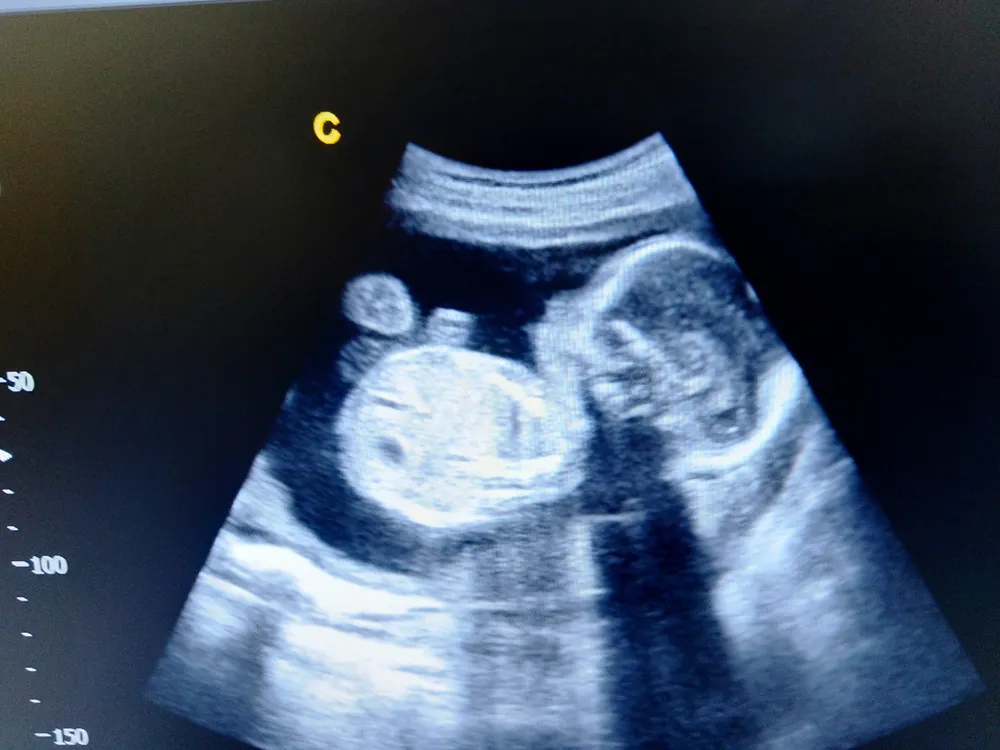

2. Hình ảnh siêu âm thai 20 tuần trong bụng mẹ

Các chỉ số sinh trắc của thai 20 tuần khỏe mạnh gồm:

- Đường kính lưỡng đỉnh (BPD): 41-52mm

- Chu vi vòng đầu (HC): 157-188mm

- Chu vi vòng bụng (AC): 132-167mm

- Chiều dài xương đùi (FL): 28-36mm.